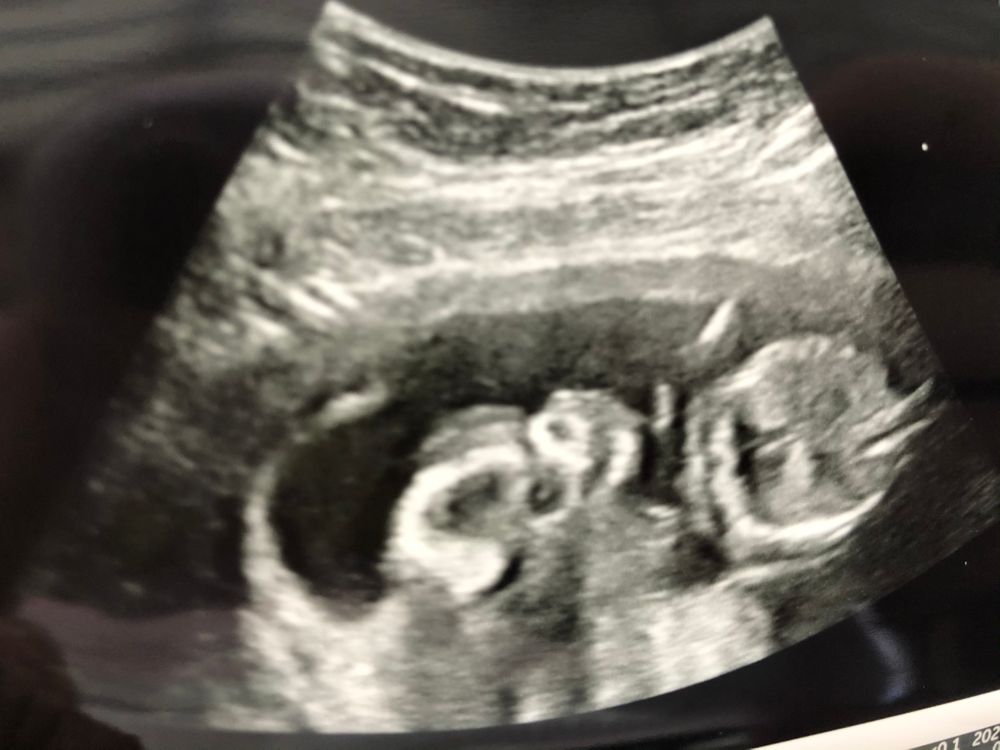

Вот и узи. Пол тут не погадать, а вот как насчёт отслоек не видно( простите, с беременностью последний мозг потеряла)